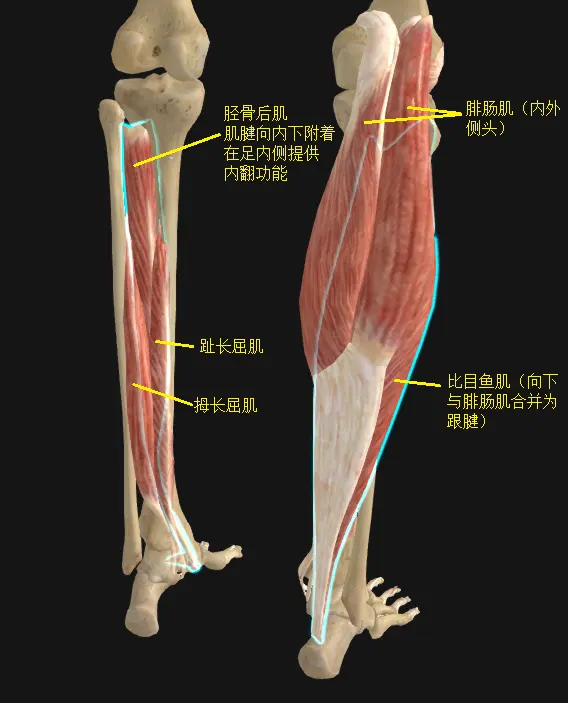

踝关节的跖屈肌有小腿三头肌(腓肠肌+比目鱼肌),趾长屈肌,胫骨后肌,拇长屈肌。

踝关节的跖屈肌有小腿三头肌(腓肠肌+比目鱼肌),趾长屈肌,胫骨后肌,拇长屈肌。

外翻肌有腓骨长肌,腓骨短肌,第三腓骨肌。